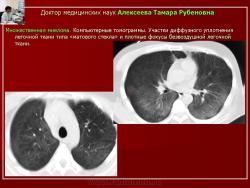

При рентгенологическом исследовании отмечалось понижение воздушности легочной ткани, сопровождающееся усилением легочного рисунка в нижних отделах с обеих сторон и появлением участков уплотнения легочной ткани без четких контуров. При компьютерно-томографическом исследовании выявлялись различных размеров участки «матового стекла» с нечеткими контурами, отмечалось утолщение внутридолькового и междолькового интерстиция. На фоне «матового стекла» прослеживались сосуды, сегментарные и субсегментарные бронхи. В субплевральных отделах определялись более плотные фокусы безвоздушной легочной ткани (рис. 21, 22).

Рис. 21. Б-ной М. Множественная миелома.

Обзорные рентгенограммы с интервалом 3 недели. В средостении - увеличенные лимфатические узлы. В нижних отделах легких рисунок усилен, малоинтенсивные участки уплотнения легочной ткани.

Рис. 22. Тот же б-ной М. Множественная миелома.

Компьютерные томограммы. Участки диффузного уплотнения легочной ткани типа «матового стекла» и плотные фокусы безвоздушной легочной ткани.

Согласно нашим исследованиям, типичным рентгенологическим признаком пневмоцистной пневмонии на ранних этапах являлось наличие уплотнений легочной ткани, обусловленные понижением её воздушности преимущественно в средних и нижних отделах легких с обеих сторон в виде различных размеров зон «матового стекла» с нечеткими контурами. В субплевральных отделах определялись более плотные фокусы безвоздушной легочной ткани.